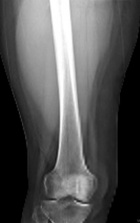

66 year old woman c/o right thigh pain x11 weeks, 20 lb weight loss in 5 weeks

Zoom image: Radiological image Radiological image.